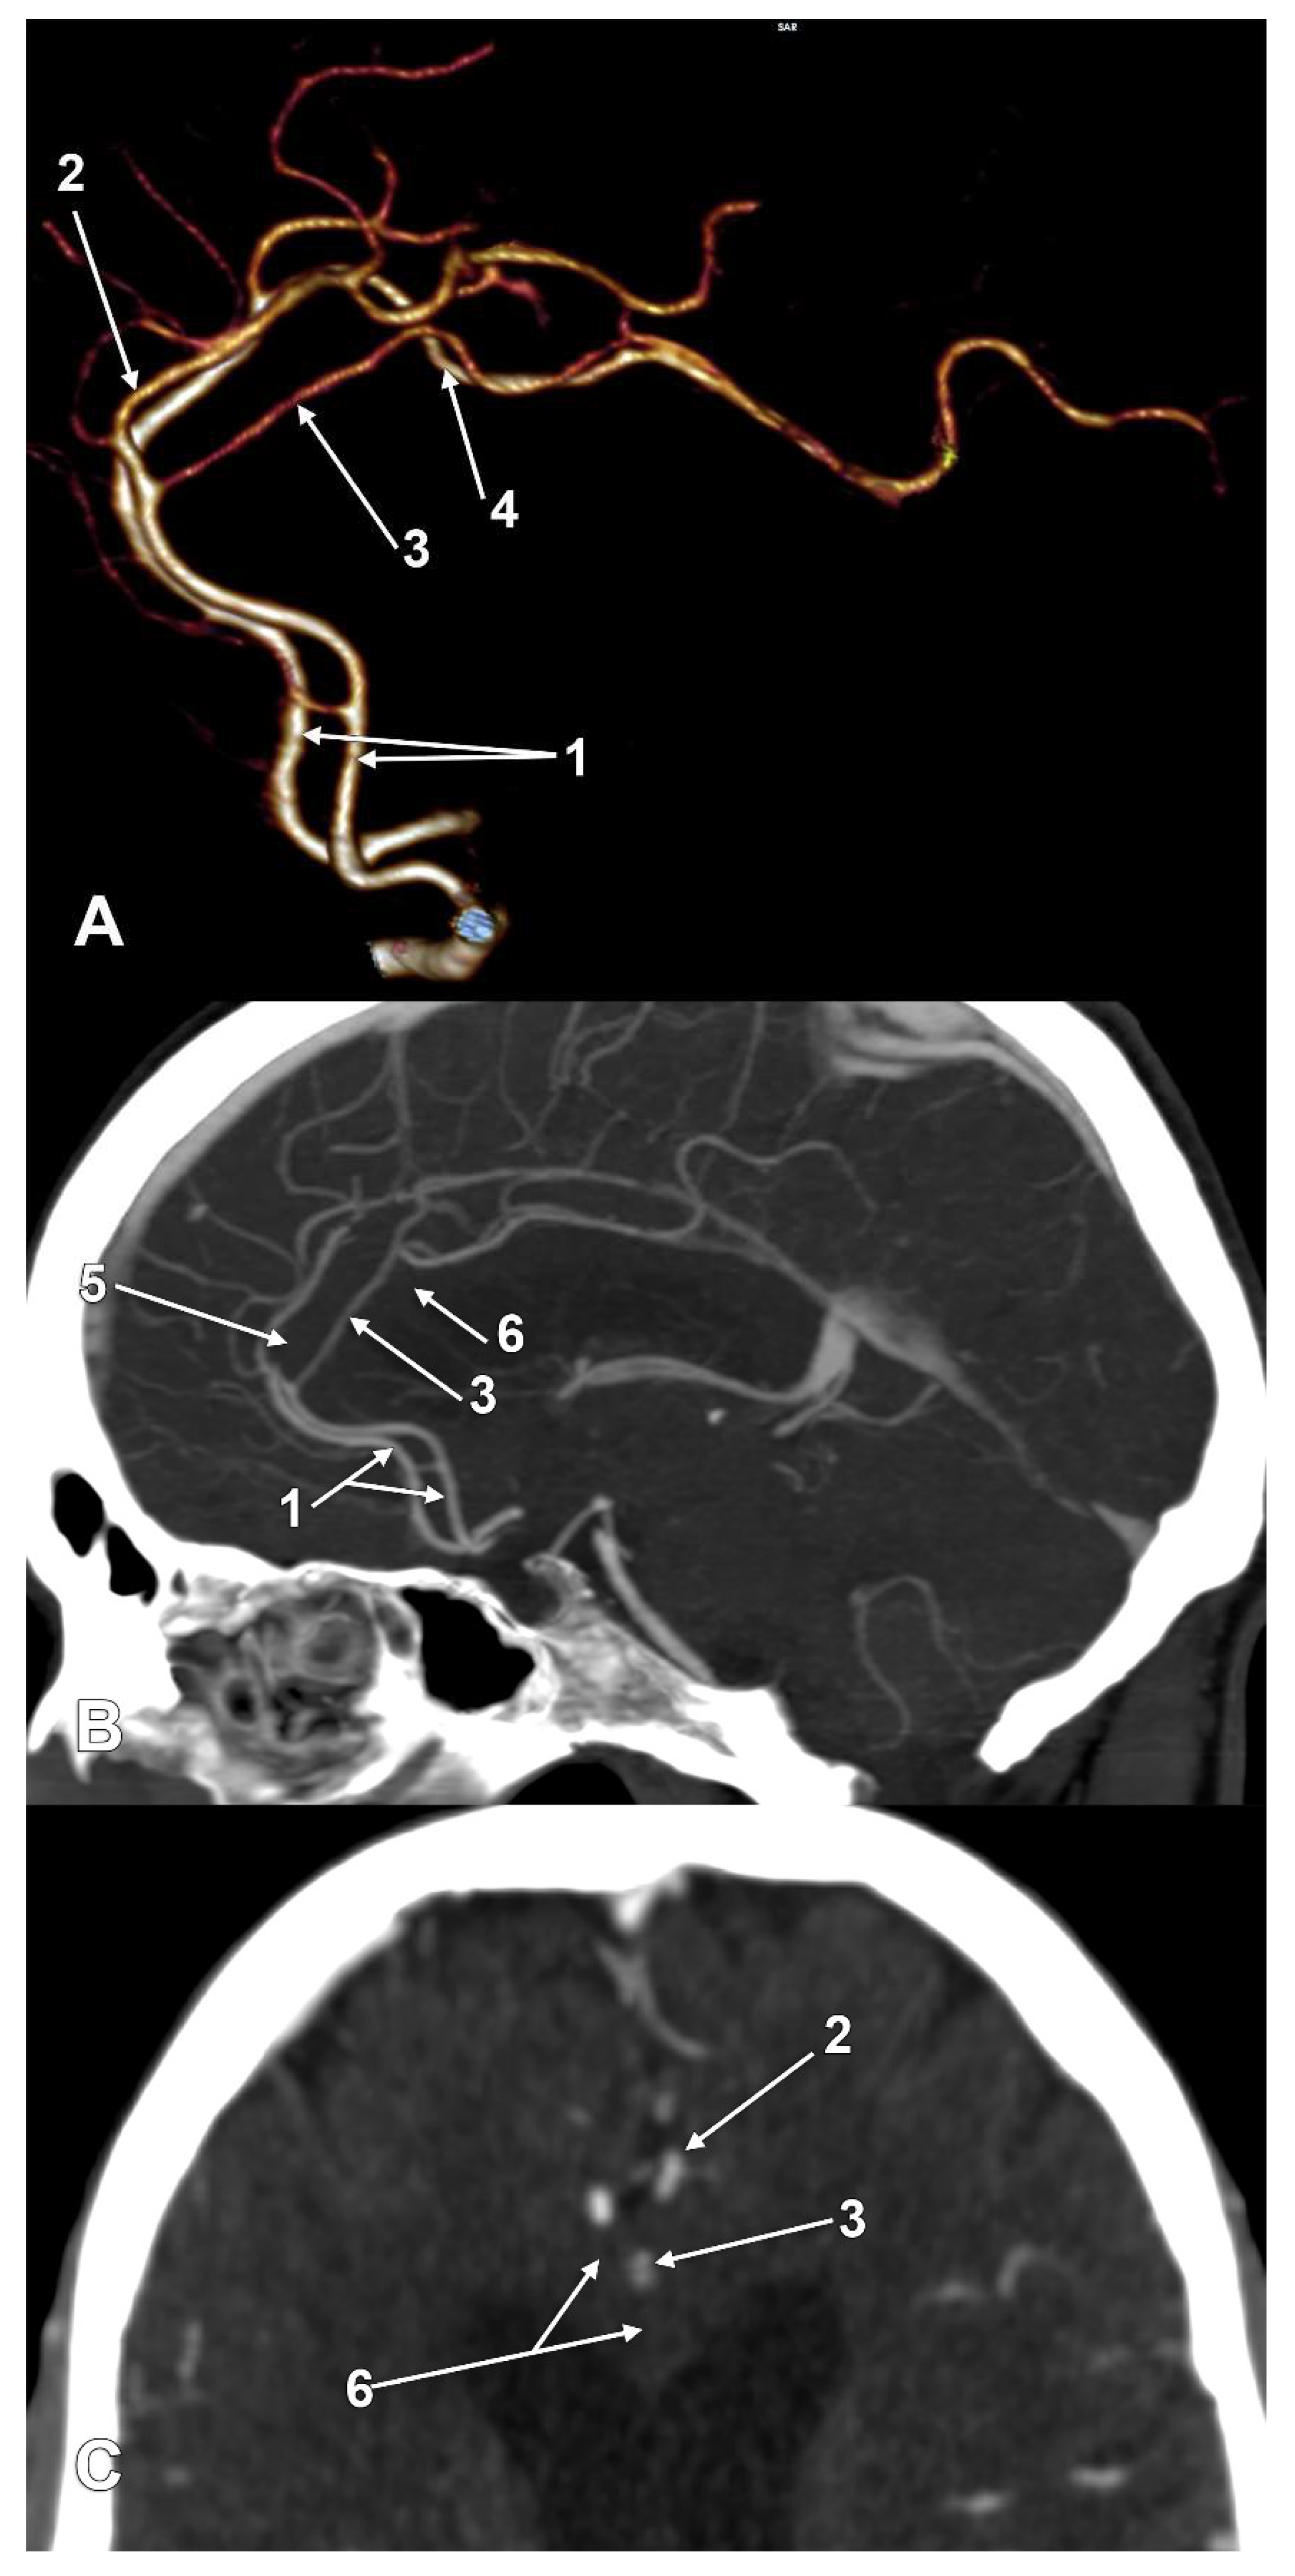

The incidences of the PCalA types, as defined in the 90 sides that were investigated, resulted in a decreasing order, as follows: PCalA type 1 (Figure 1A,C,F) was found in 46/90 sides (51.11%), type 10 (Figure 1B) was found in 13/90 sides (14.44%), type 7 (Figure 1C) was found in 7/90 sides (7.78%), type 2b (Figure 1D) was found in 6/90 sides (6.67%), type 8 (Figure 1B) was found in 5/90 sides (5.56%), types 3 (Figure 1E) and 4 (transcallosal course of the PCalA) (Figure 2 and Figure 3, Video S1) were found each in 3/90 sides (3.33%), types 2a (Figure 1E,F) and also 6 (Figure 4A), were found in 2/90 sides (2.22%), and types 5 (Figure 4B), 9 (Figure 4C), and 11 (triple PCalA) (Figure 4D) were each found in 1/90 sides (1.11%) (Table 1).

Figure 2. Type 4, pericallosal artery coursing through the corpus callosum. (A) Three-dimensional volume rendering, left lateral view; (B) Mediosagittal slice through the corpus callosum. (C) Axial slice through the corpus callosum: 1. anterior cerebral arteries; 2. left callosomarginal artery; 3. transcallosal course of the left pericallosal artery; 4. right pericallosal artery; 5. genu of corpus callosum; 6. body of corpus callosum.